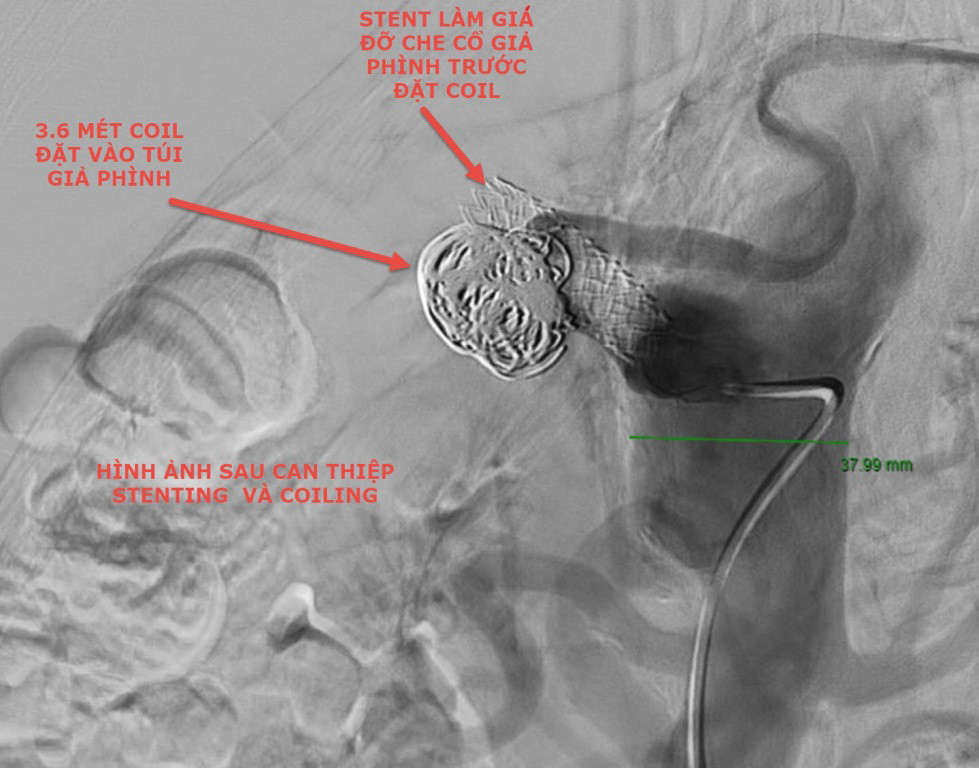

Hình ảnh DSA sau khi can thiệp mạch tạng cho người bệnh (ảnh:BVCC) Sau khi thực hiện CT và nội soi dạ dày tá tràng, các bác sĩ cho biết anh V bị xuất huyết tiêu hóa trên nghi do chảy máu đường mật từ khối máu tụ và giả phình kèm hiện tượng tắc mật do chèn ép. Khối máu tụ to với đường kính hơn 8cm (nằm vùng đầu và thân tụy) do giả phình động mạch (đường kính 28mm) đang hoạt động ngay phần chia đôi của động mạch thân tạng gây chèn ép gây tắc mật và nguy cơ vỡ lan rộng (do chảy máu tiếp diễn). Các xét nghiệm cho thấy rõ tình trạng người bệnh bị vàng da tắc mật như bilirubin tăng cao, men gan tăng gần 1000 UI/ml và thiếu máu.

Bệnh nhân được khám lại trước khi xuất viện (ảnh: BVCC) “Sau khi cân nhắc các phương án điều trị cho người bệnh và kết quả chụp mạch máu xóa nền, chúng tôi đã quyết định can thiệp lần đầu bằng cách đặt khung hợp kim có màng phủ để che túi giả phình và chuyển dòng chảy vào động mạch gan. Đây là phương pháp an toàn nhất ở thời điểm hiện tại cho người bệnh, nhưng đòi hỏi kỹ thuật cao trước các nguy cơ tai biến (như không kiểm soát chảy máu khi có biến chứng chảy máu trong thủ thuật, nguy cơ tắc động mạch lách, động mạch gan và không che hết cổ giả phình….) đồng thời cân nhắc hướng xử lý tiếp theo tùy theo diễn tiến bệnh ngay sau can thiệp” - BS Dương chia sẻ.